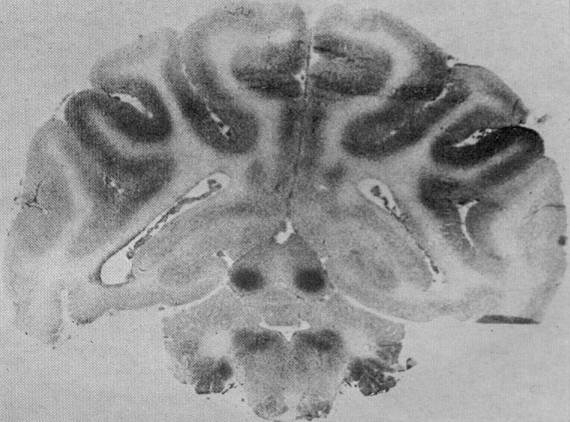

Figures 19 and 7 below, from Myers (1972) paper, show how blood flow in the

brain is affected by what he termed "partial asphyxia," or oxygen insufficiency

caused by impaired maternal circulation to the placenta (figure 19).  With

diminished oxygen, circulation to the inferior colliculi and other brainstem nuclei

of high metabolic rate is increased (a protective mechanism), while blood flow to

the metabolically less active cerebral cortex is severely diminished.

Compare figure 19 B with figure 7, showing normal blood flow pattern, which is

highest in the brainstem, especially the inferior colliculi.

Fig 19.  Autoradiographs

demonstrating alterations

in fetal cerebral blood flow

produced by in utero fetal

partial asphyxia.  The fetus

exposed to less severe

asphyxia (A) exhibited

decreases in blood flow

throughout major extents of

the cortical gray matter and

the centrum semiovale.

Only the striated cortex

region manifested

minimally in the way of

blood flow alteration.  In

some areas, blood flow

reductions as large as 50

percent are observed in

this brain.  With the

development of severe

hemispheral swelling as

indicated by the

compressions of the

superior cerebellar

surfaces, a total loss in

hemispheral perfusion

results (B).  while the

brainstem is little affected,

the cerebellum may exhibit

symmetrical zones of

diminished perfusion.